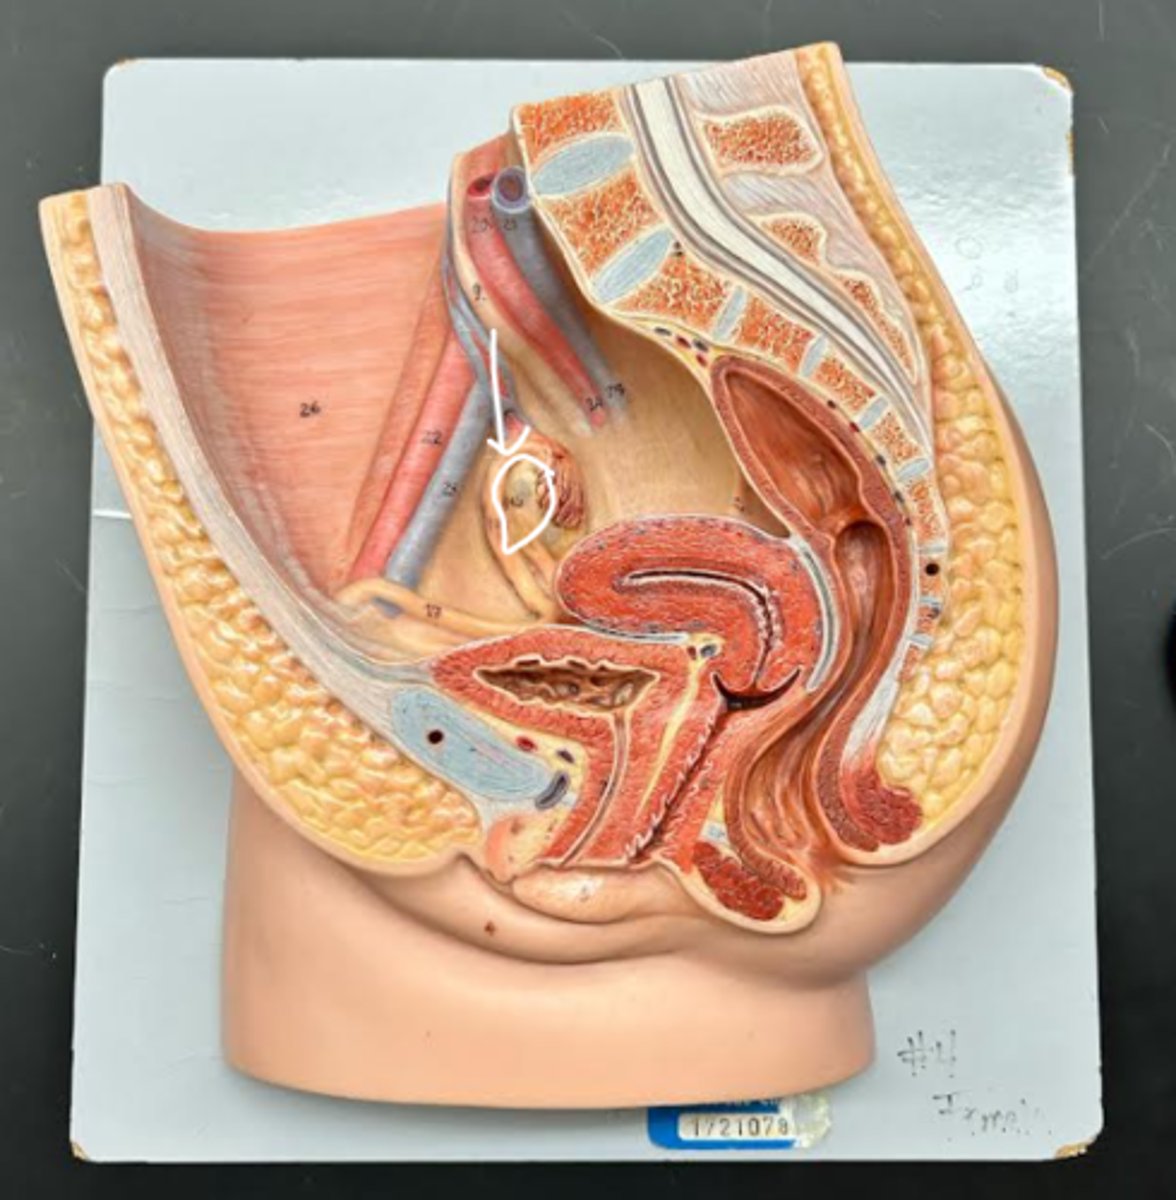

Chapter 29 Anat Phys: Female Reproductive System

Vagina

Vaginal orifice

Hymen

Vaginal fornix

Ovary

Fallopian tube

Fimbriae

Infundibulum

Ampulla

Isthmus

Uterus

Perimetrium

Myometrium

Endometrium

Fundus

Body of uterus

Cervix

Internal os

Cervical canal

External os

Labia majora

Labia minora

Prepuce

Vestibule

Clitoris

External urethral orifice